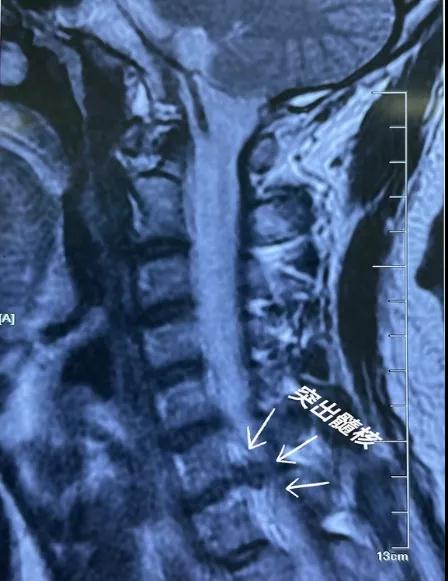

术前核磁共振

38岁的康先生在一家国企上班,长期伏案工作的他1个月前出现颈痛,伴有右前臂放射痛和麻木,经休息和保守治疗无效,且逐步加重,彻夜难眠。患者曾于红会医院就诊,磁共振显示:颈6-7椎间盘突出,相应脊髓及神经受压,建议行颈前路开刀融合固定手术。经多方面考虑,最终决定给予患者采取颈椎内镜后路Key-hole手术。目前,颈椎内镜应用于神经根型颈椎病,利用Key-hole技术对脊髓及神经根旁中央的腹侧压迫进行减压取得了很好的疗效。